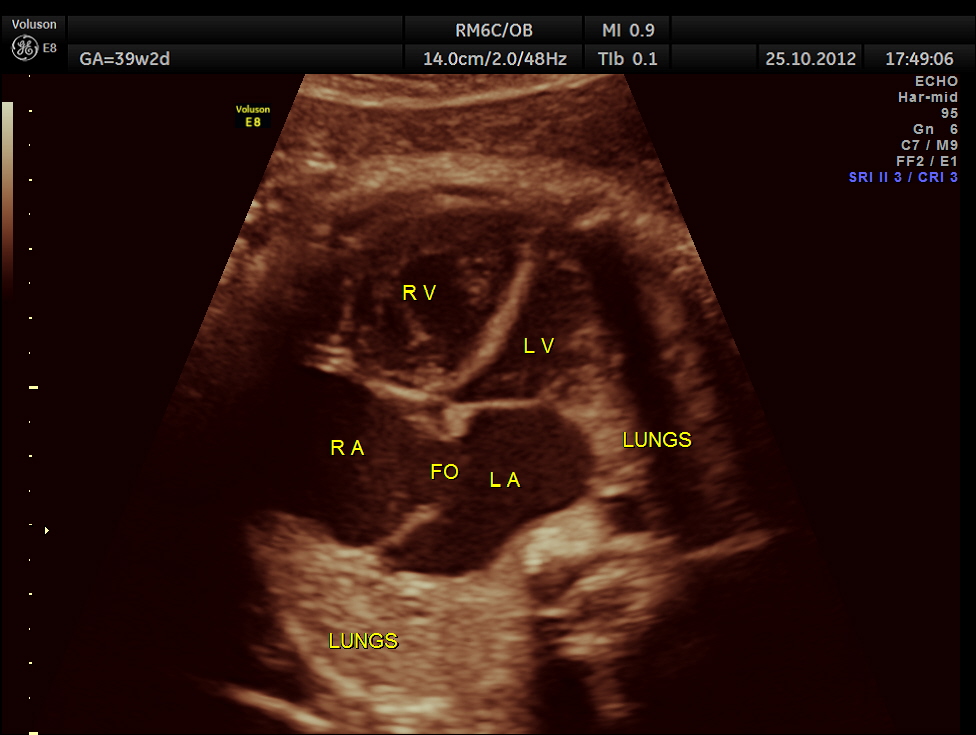

THIS FETUS HAD SEVERE FETAL ANEMIA WITH CARDIAC FAILURE LEADING TO CARDIOMEGALY WITH MITRAL, TRICUSPID AND PULMONARY REGURGITATION .NO OTHER OBVIOUS CARDIAC ANOMALY WAS MADE OUT . THE VENO ATRIAL , ATRIO VENTRICULAR AND VENTRICULO ARTERIAL CONCORDANCE APPEARED TO BE NORMAL; NO SEPTAL DEFECT WAS MADE OUT.